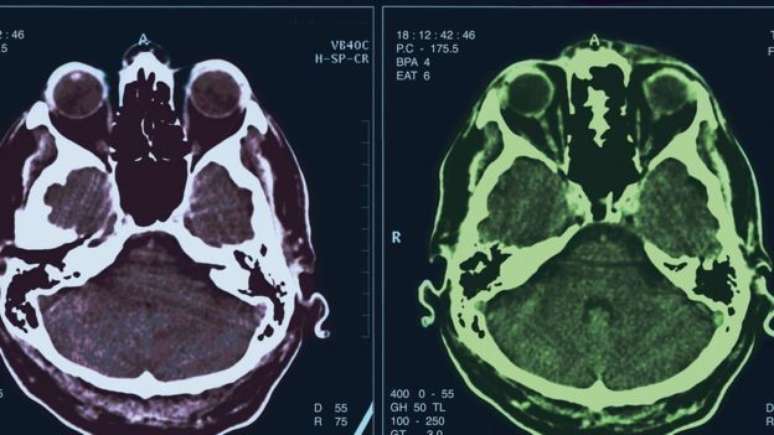

O novo estudo sugere que um em cada 11 casos de psicose pode envolver anticorpos que atacam determinadas partes do cérebro.

Foto: Thinkstock